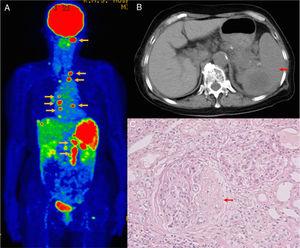

Findings of 18F-fluorodeoxyglucose-positron emission tomography/computed tomography (FDG-PET-CT), abdominal enhanced CT, and renal biopsy. (A) FDG-PET-CT shows FDG accumulation in the cervical, thoracic, and abdominal lymph nodes (yellow arrows) and spleen, indicating widespread lymphadenopathy and splenomegaly. (B) Abdominal enhanced CT shows splenomegaly (red arrow) with a low-density area. (C) Renal biopsy specimen reveals crescentic glomerulonephritis with fibrocellular crescent (arrow, Periodic acid-Schiff stain).

A 70-year-old Japanese woman with a 57-year history of hepatitis C virus presented with nausea, abdominal pain, and renal dysfunction. Physical examination revealed splenomegaly. Blood examination revealed elevated levels of C reactive protein (2.7mg/dL), serum creatinine (2.46mg/dL), blood urea nitrogen (22mg/dL), and uric acid (7.8mg/dL). Test for myeloperoxidase-antineutrophil cytoplasmic antibody (MPO-ANCA) was positive (71.2U/mL). Urinalysis showed proteinuria (0.56g/gCr) and microhematuria (>100 red blood cells/high-power field). 18F-fluorodeoxyglucose-positron emission tomography/computed tomography (FDG-PET-CT) revealed FDG accumulation in the cervical, thoracic, and abdominal lymph nodes and spleen (Fig. 1A). Abdominal computed tomography revealed splenomegaly with a low-density area (Fig. 1B). Renal biopsy specimen showed crescentic glomerulonephritis (Fig. 1C). Abdominal paraaortic lymph node biopsy revealed diffuse large B cell lymphoma (DLBCL). Based on these findings, the patient was diagnosed with ANCA-associated vasculitis (AAV) and DLBCL with suspected splenic DLBCL. Treatment with R-CHOP regimen was initiated, and her renal function improved. However, no remission was noted for the DLBCL. The patient died 4 months later.